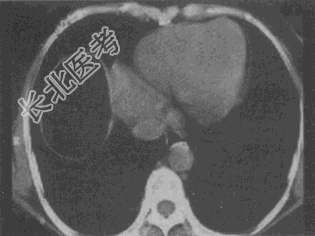

- 单项选择题患者男,30岁, 右下腹稍隆起,CT检查如图, 最可能的诊断为

A、右膈下脓肿

B、间位结肠

C、右膈下脂肪瘤

D、右下肺肺大疱

E、右下肺炎